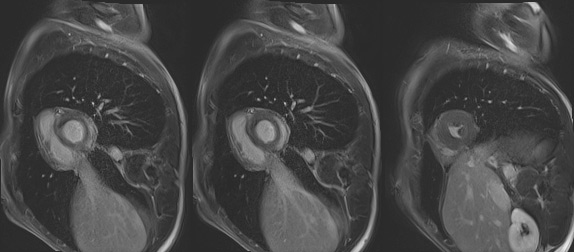

Figure 1A : Séquence Ciné-IRM coupe 4 cavités

Figure 1B : Séquence Ciné-IRM coupe 3 cavités

Figure 1C : Séquence Ciné-IRM coupe 2 cavités